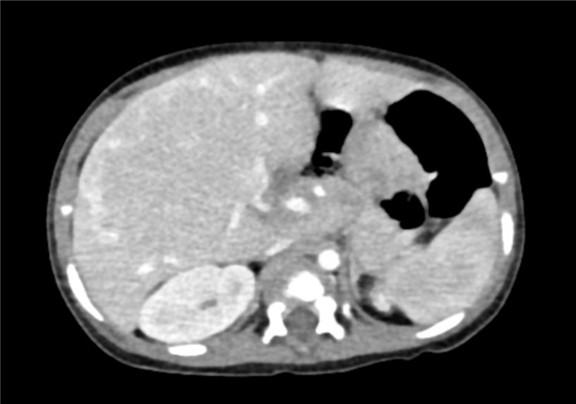

术前CT检查:

动脉期

下腹部增强CT示:肝内巨大占位,考虑肝母细胞瘤可能性大,建议MRI平扫+增强进一步检查,腹腔、腹膜后多发肿大淋巴结影,考虑转移瘤可能性大,肝内多发结节,考虑血管瘤可能性大,建议随访